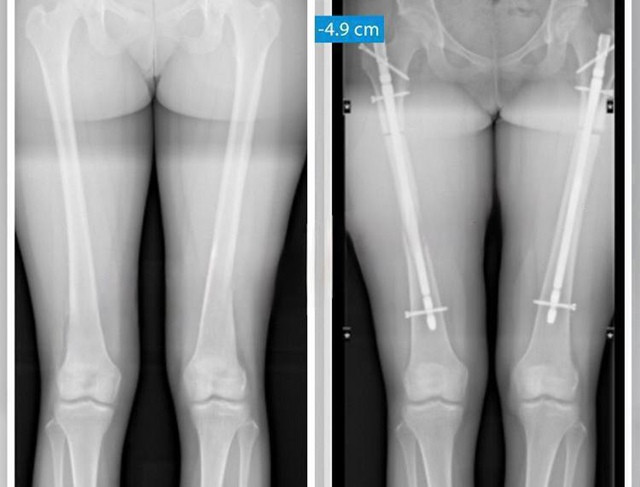

Дурка: операции по укорочению ног набирают популярность в Стамбуле — женщины специально уменьшают рост, чтобы завести отношения.

Хирурги спиливают часть бедренной или большеберцовой кости, уменьшая рост на 3–5,5 см. Например, одна пациентка снизила свой рост с 172 до 167 см.